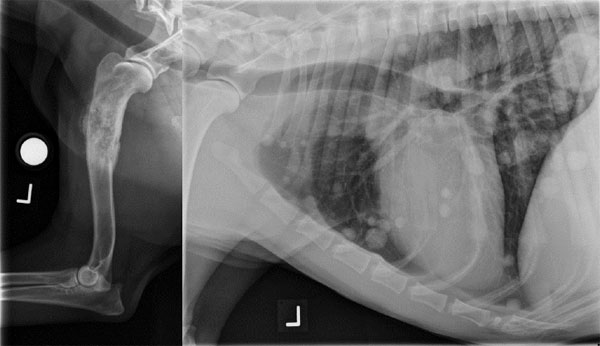

Οστεοσάρκωμα του σκύλου. Διάγνωση, θεραπευτικές στρατηγικές και αισιοδοξία για το μέλλον!

Το 2ο διαδικτυακό σεμινάριο της ΕΛΕΚΖΣ αφορά το οστεοσάρκωμα στο σκύλο. Θα αναπτυχθούν η διάγνωση και οι θεραπευτικές επιλογές που υπάρχουν, ενώ θα συζητηθεί ο ρόλος που μπορεί στο μέλλον να διαδραματίσει η ανοσοθεραπεία στην αντιμετώπισή του. Με την ολοκλήρωση του σεμιναρίου οι συμμετέχοντες θα έχουν κατανοήσει: Τη διαγνωστική προσέγγιση Τη κλινική σταδιοποίηση Τους προγνωστικούς παράγοντες Το μέλλον της ανοσοθεραπείας στη νόσο